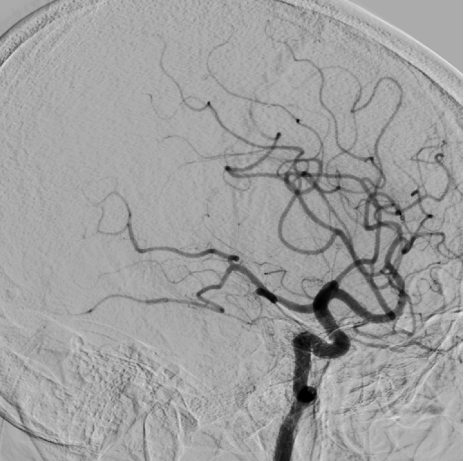

术中脑血管造影证实责任血管为左侧大脑中动脉M2上干闭塞。M2段血管取栓治疗属于MeVO取栓。

这类手术被称为“刀尖上的舞蹈”:一是M2上干管腔细小、路径迂曲,操作空间极小;二是血管壁脆弱,易破裂出血;三是若血管未及时开通,患者可能终身遗留神经功能缺损。

术中,介入医生凭借丰富的临床经验与精准的操作技巧,在纤细迂曲的血管通道中谨慎操控器械,逐步推进至血栓位置,最终成功将M2上干内的血栓取出,实现血管再通。